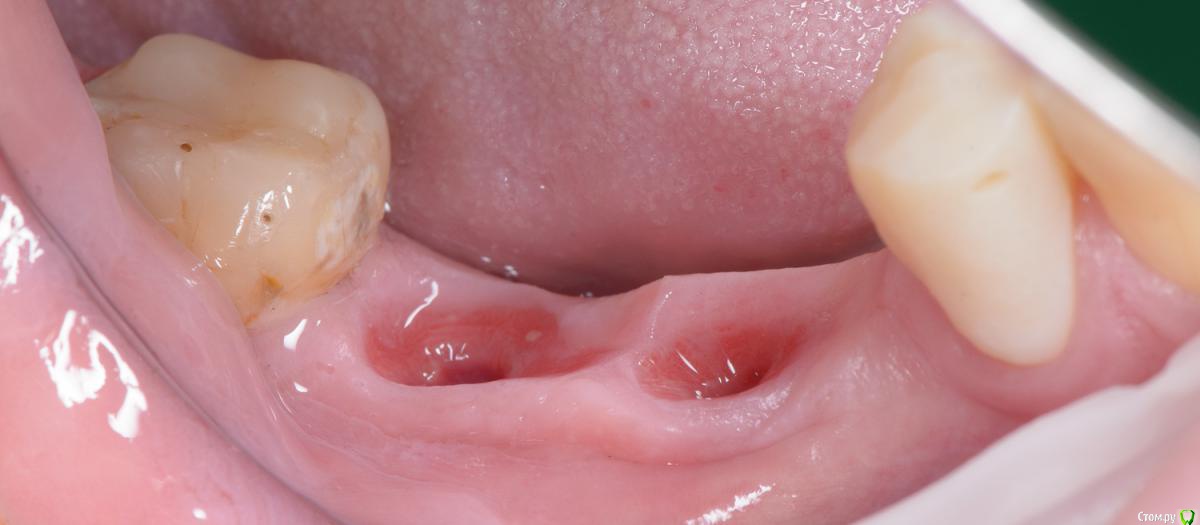

Популярный пост Mane Опубликовано 8 февраля, 2015 Популярный пост Поделиться Опубликовано 8 февраля, 2015 Зафиксировал в субботу. Собственно удалось размоделировать десну просто временной коронкой с заданным профилем прорезывания. Но для этого необходимо было выполнить ряд условий. Каких, доктора? http://i1218.photobucket.com/albums/dd412/Edikn73/emergence%20profile/Emergenceprofile001_zps040f2603.jpg http://i1218.photobucket.com/albums/dd412/Edikn73/emergence%20profile/Emergenceprofile002_zpsaa7acb0b.jpg http://i1218.photobucket.com/albums/dd412/Edikn73/emergence%20profile/Emergenceprofile003_zps259f0885.jpg http://i1218.photobucket.com/albums/dd412/Edikn73/emergence%20profile/Emergenceprofile004_zps6a15b901.jpg http://i1218.photobucket.com/albums/dd412/Edikn73/emergence%20profile/Emergenceprofile005_zps51a41bc2.jpg http://i1218.photobucket.com/albums/dd412/Edikn73/emergence%20profile/Emergenceprofile006_zps3c83a34d.jpg http://i1218.photobucket.com/albums/dd412/Edikn73/emergence%20profile/Emergenceprofile007_zpsba4d3d78.jpg 26 Ссылка на комментарий

Mane Опубликовано 10 февраля, 2015 Автор Поделиться Опубликовано 10 февраля, 2015 По поводу профиля прорезывание интересен Ваш протокол. Менялся ли ФДМ на более широкий, делались ли насечки на десне во время фиксации времяхи? Во первых - это заглубление платформы импланта - от будущего зенита до платформы - 3,5 мм . если этого не сделать - ничего не полуитсяпосле тонкого фдм зафиксировал временную коронку с небольшим надрезом по контактам. отдыхала с времянкой 1,5 мес.далее вы видели 1 Ссылка на комментарий

artemov Опубликовано 19 февраля, 2015 Поделиться Опубликовано 19 февраля, 2015 Здорово! Дабы не создавать новую тему, добавлю пару фото. Тоже без пластики десны, тоже субкрестально, только временные коронки! Толстый биотип решает 4 Ссылка на комментарий